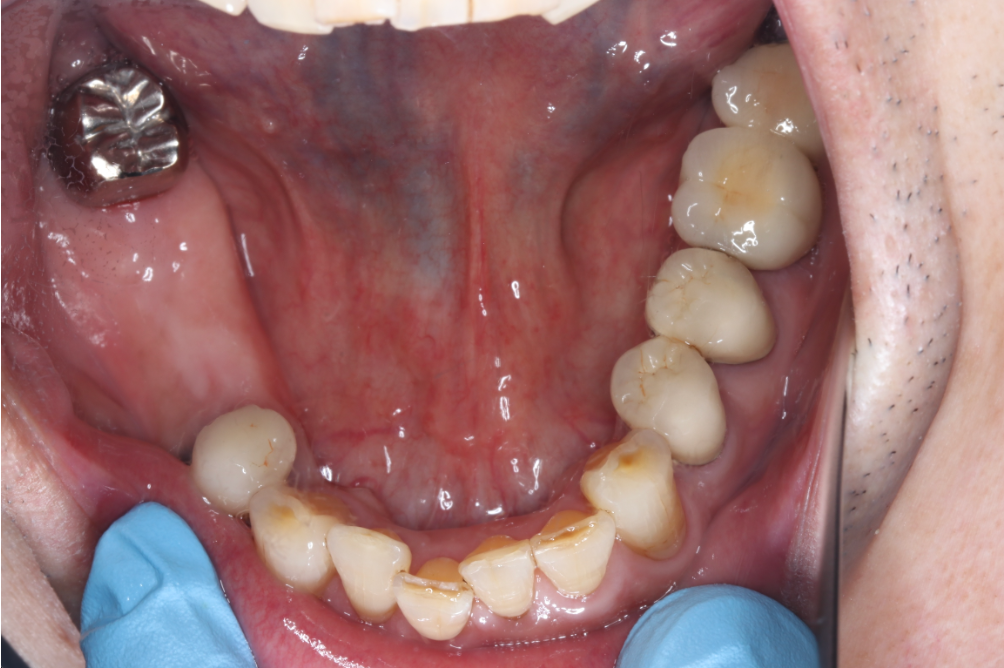

インプラント症例②

年齢 50代男性

治療期間 4ヶ月

インプラントメーカ ジンマーインプラント

治療内容 カスタムアバットメント、上部ジルコニア

治療箇所 左下6番

治療費用 380,000円